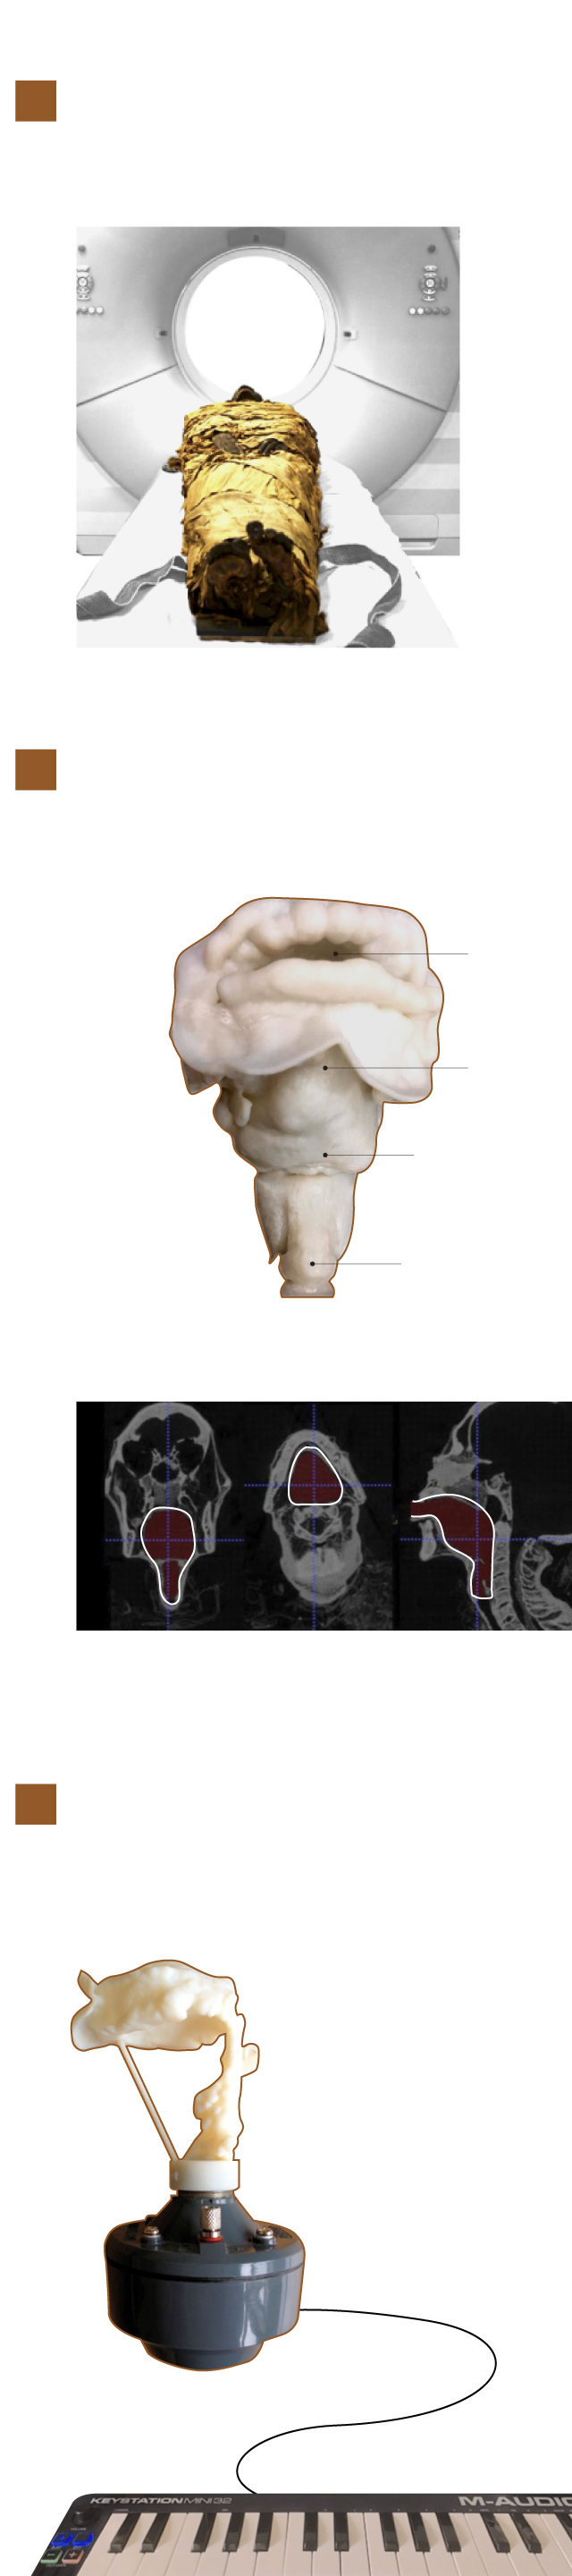

La momia, en un estado óptimo de conservación, fue introducida en un escáner para conseguir una imagen del tracto vocal de Nesiamón.

Escáner de rayos X

Con esta imagen se generó, en una impresora 3D, una cavidad oral, la faringe y la laringe con las mismas dimensiones de la momia.

Boca

Faringe

Laringe

Tráquea

Reconstrucción 3D

Imagen del tracto vocal de Nesiamón

Los investigadores utilizaron un aparato de su invención llamado órgano de tractos vocales conectado a un teclado con el que consiguieron generar el sonido.

Órgano de tractos vocales